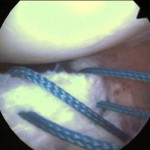

a) Inestabilidad fémoro-rotuliana: freecuente en mujeres jóvenes, deportistas, hiperelásticas y con escasa musculatura cuadricipital. Generalmente se soluciona con tratamiento rehabilitador, pero en casos recidivantes puede ser necesario recurrir a la cirugía, como muestra el caso de lasfotos que se muestran a la derecha, que representan a un deportista que sufrió varias luxaciones de rótula (desplazamiento fuera de su sitio anatómico) que requirió cirugía artroscópica donde se evidenció daño del cartílago de la rótula.

El TAC o escáner sirve para estudiar en profundidad el caso, como este que se muestra a la derecha donde se ve perfectamente la basculación de la rótula con desplazamiento externo, con lo que se encuentra subluxada o fuera del canal troclear.

La siguiente imagen nos muestra unas rodillas con pocas posibilidades de sufrir patología rotuliana. La última nos muestra la técnica artroscópica de Detrisac con apertura del alerón externo y plicatura del interno.